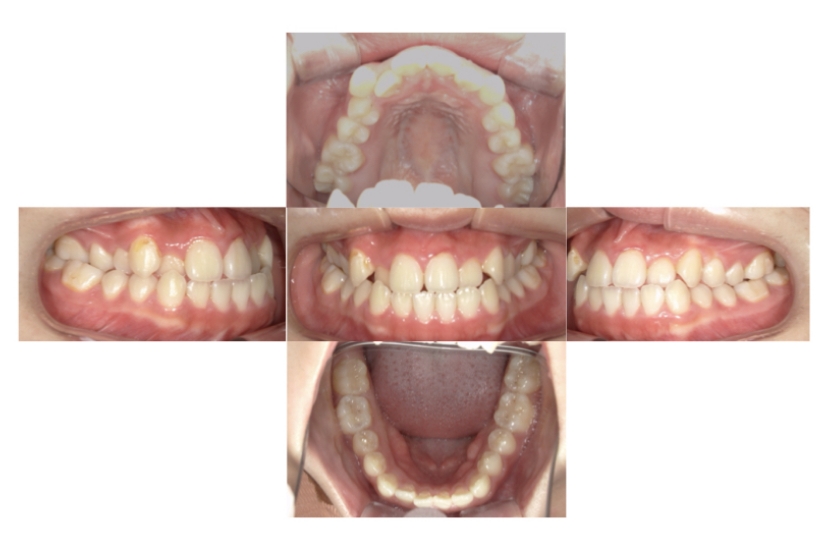

BEFORE

AFTER

上下顎前突、叢生(上下出っ歯、上下の前歯のガタガタ)のケースです。

装置はラビアル(上下表側)で、上下顎の小臼歯を4本抜歯を行っています。抜歯したスペースを使って、上下の前歯の後方移動と叢生(ガタガタ)の改善を行っています。

主訴 前歯のガタガタと口元がでているのが気になる。

年齢・性別 30歳 女性

お住まいの地域 東京都大田区

治療方針 抜歯スペースを利用して上前歯の叢生(ガタガタ)と口元突出の改善

抜歯部位 上下顎左右第一小臼歯

使用装置 ラビアル(上下表側)、顎間ゴム

治療期間 1年11か月

治療回数 13回

リテーナー クリアリテーナー